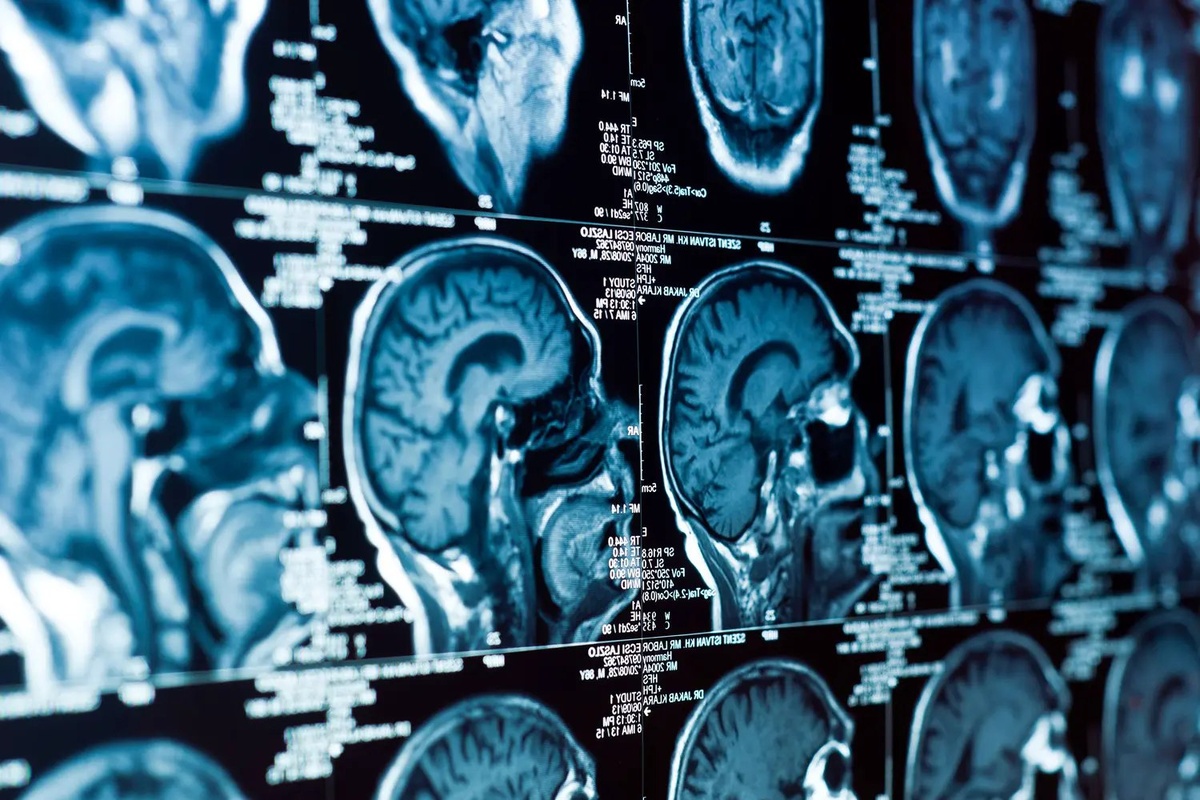

Ученые из Лозанны нашли способ бороться со злобной глиобластомой! Они выяснили, что блокировка белка ADAR1 замедляет рост опухоли и даже может уменьшить риск её появления на 50%! Эксперименты на мышках и клетках человека показали крутые результаты. Теперь учёные ищут лекарство, которое будет блокировать этот ADAR1, и это – реально большая надежда для всех, кто борется с этой гадостью!